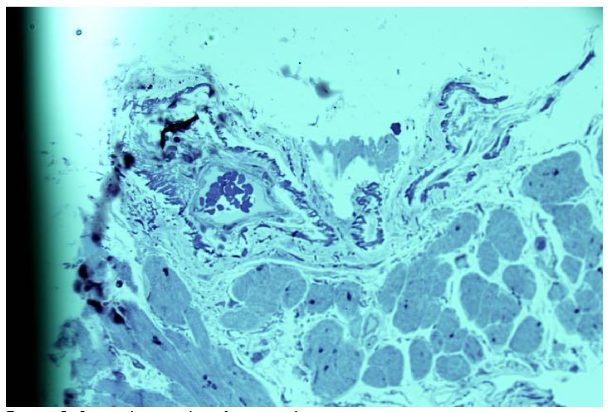

In cases of single de novo arteriole formation, the pathological vascular growth score reached up to 3 -4 points.17 In other patients, de novo arterioles exhibited variable lumen sizes, with multiple aligned or isolated lumens, sometimes associated with residual shared membranes.

One arteriole showed chambers indicative of a separating convolution. Pathological arteriolar growth in this patient was also scored 4 due to increased de novo vessel formation.

The observed arteriolar growth sometimes resulted in highly irregular forms. Formation of pseudo-vessels occurred through protrusion of one arteriolar wall into the lumen, and growing walls occasionally created new vessels with dual lumens.

De novo formation from these vessels typically exhibited thickened walls and narrow lumen profiles.